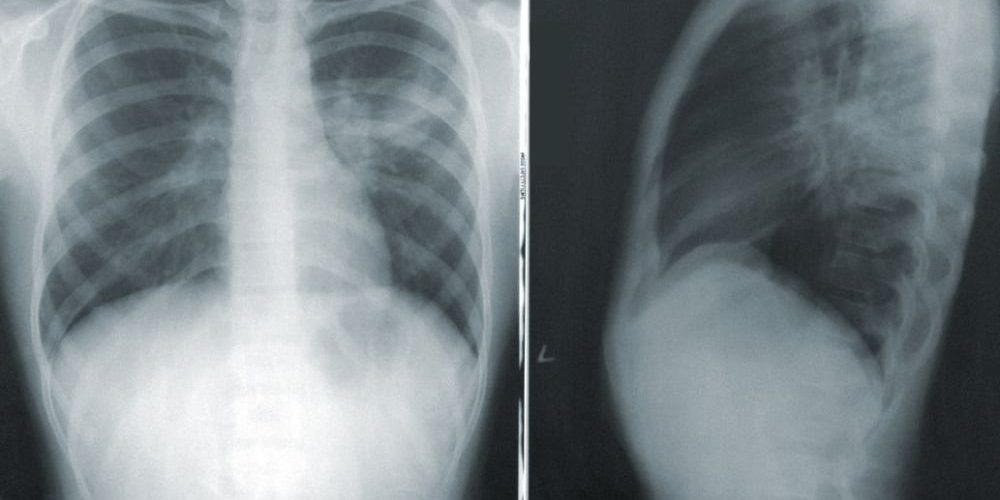

Эксперты опасаются, что тесты на уровень «хорошего» или «плохого» холестерина не дают адекватной картины здоровья человека в целом. Также появляется всё больше доказательств того, что для понимания ситуации с самочувствием пациентов и того, нужны ли статины, нужны другие исследования. Они позволят предупредить развитие болезней сердца еще до появления характерных симптомов. Одним из таких методов более точной диагностики является рентгеновское исследование артерий.

С его помощью можно проверить наличие отложений кальция, скапливающихся в жировые бляшки, из-за которых отвердевают кровеносные сосуды сердца. Обычные анализы крови могут показать количество циркулирующего в кровотоке холестерина, но тест на кальций более полезен для определения этих отложений в качестве маркеров будущих болезней сердца и инсультов. Вот поэтому рентген и является более надежным инструментом определения необходимости выписки статинов.